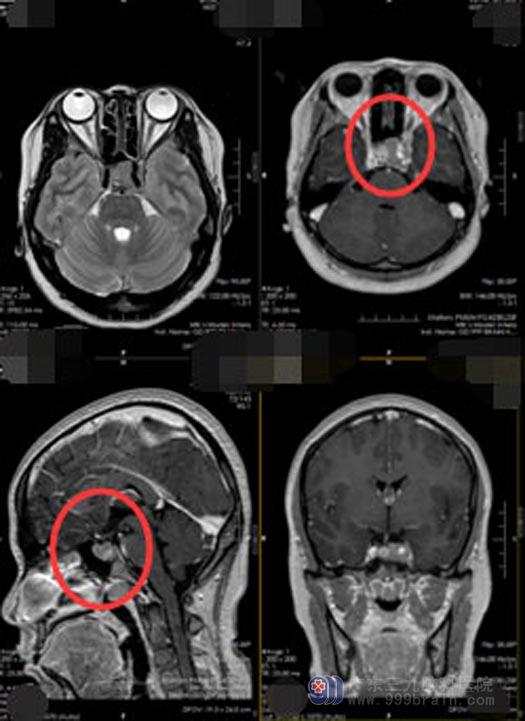

入院后进一步检查发现,垂体催乳素:2458ug/L(正常值:4.79-23.3ug/L),头颅CTA示:鞍区扩大,鞍内占位性病变存在少许血供,病变包绕左侧颈内动脉海绵窦段;MRI检查结果示,鞍内偏左侧占位性病变,侵犯左侧海绵窦并包绕左侧颈内动脉,考虑垂体腺瘤。

打消了小吴的顾虑后,由医院副院长、神经外五科主任鲁明主刀,在全麻下为她行“内镜经鼻蝶侵袭性垂体瘤切除术”,术中可见垂体位于右侧,沿着肿瘤的假包膜切除肿瘤,最大限度的减少对垂体瘤的损害,肿瘤侵袭左侧海绵窦,左侧颈内动脉被包绕,肿瘤质地坚硬,左侧海绵窦内肿瘤少量残留。术后,小吴的泌乳素水平下降到458 ug/L,双眼视物较术前清晰,头痛也有了缓解。